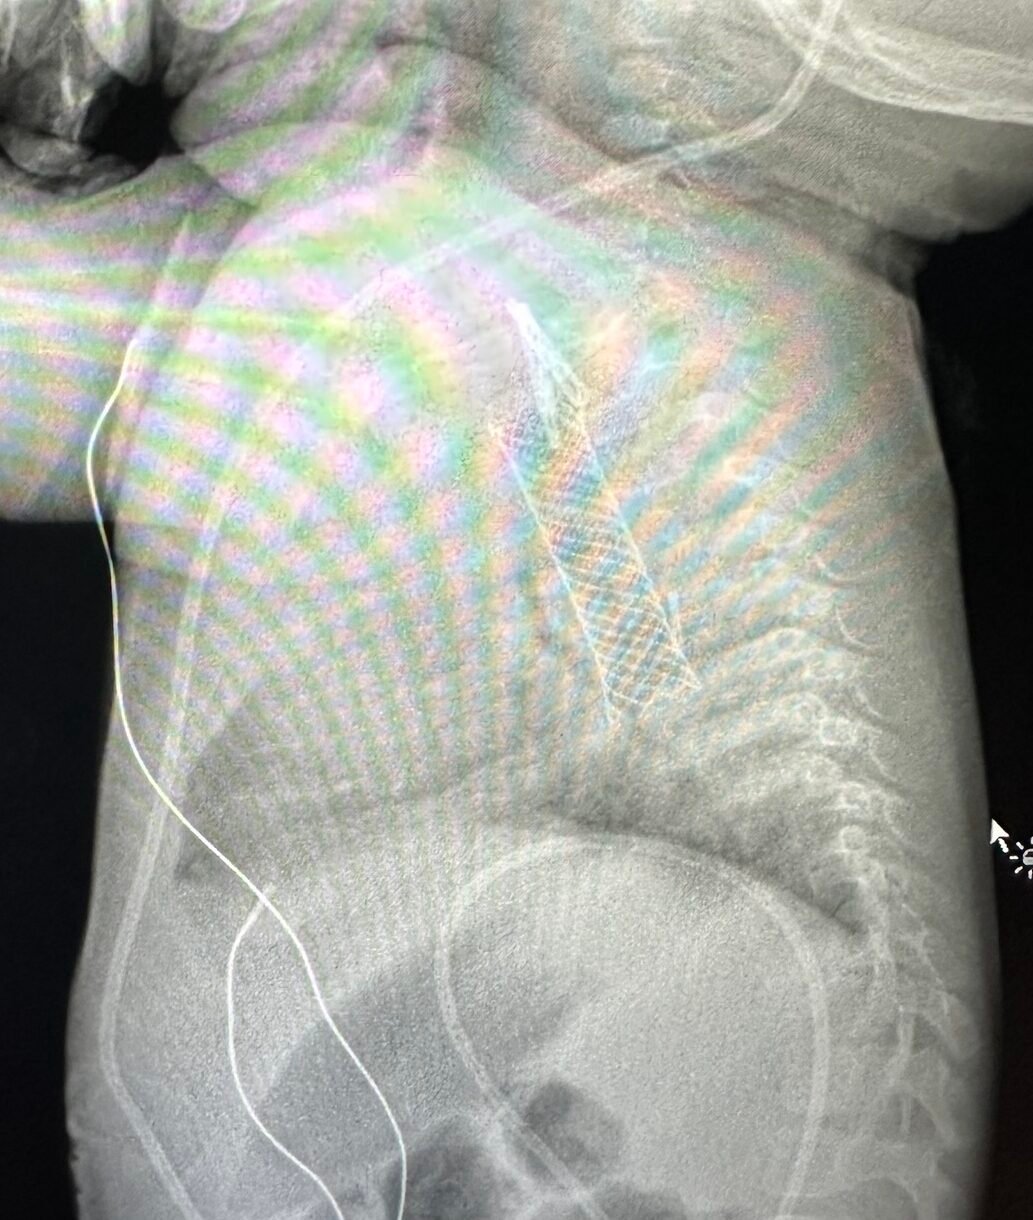

After several intense days in the hospital, we brought Imani home with a stent in her esophagus. It was meant to stay in place for nine weeks to keep her esophagus open. We were relieved to be back, but feeding her was anything but easy.

But a few months later, the signs returned. She struggled to swallow. She started refusing food again. We knew something was wrong. Back at the hospital, another scan showed her esophagus had narrowed again.

She was admitted and a second stent was placed. It was the only thing that had helped her before, and thankfully, it helped again. She started eating again, slowly but surely. Some days were easier than others. But she wanted to try and that meant everything.